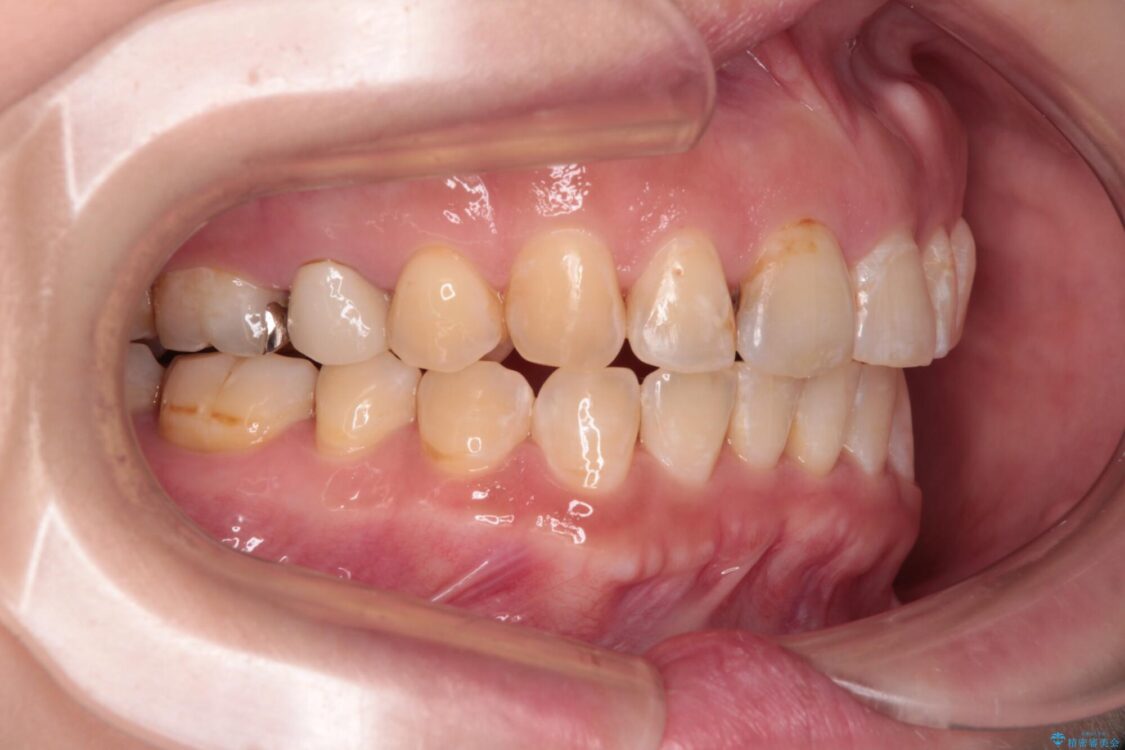

飛び出た上の前歯を気にして来院された患者様です。

奥歯の咬み合わせは、上顎歯列が理想的な一よりも数mm前方にある状態でした。

なるべく早めに治療を終えたいとのことで、補助装置を用いて上顎臼歯を後方に移動させ、同時にワイヤー装置にて整えることとしました。

治療途中

• 【モニター】飛び出た前歯を整えたい ワイヤー矯正治療 治療途中画像